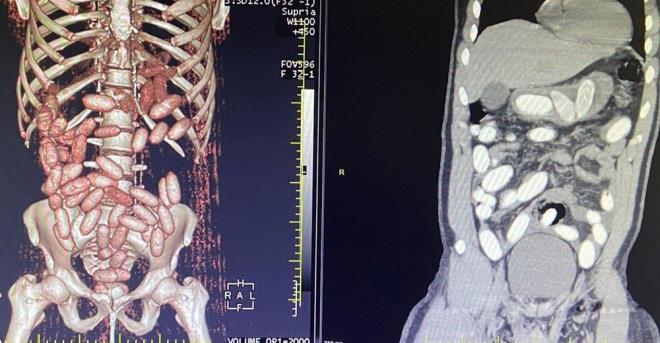

4. Yapılan ön kontrollerde şüphelilerin midelerinde normal dışı bazı materyaller olduğu belirlendi. Gümrük Muhafaza ekiplerince savcılık talimatı doğrultusunda detaylı bilgisayar tomografi çekilmesi için sağlık kuruluşuna götürülen 6 yolcunun yapılan tarama ve muayenelerinde 761 adet ve toplam ağırlığı 10 kilo 420 gram kokain tespit edildi.

Yapılan ön kontrollerde şüphelilerin midelerinde normal dışı bazı materyaller olduğu belirlendi. Gümrük Muhafaza ekiplerince savcılık talimatı doğrultusunda detaylı bilgisayar tomografi çekilmesi için sağlık kuruluşuna götürülen 6 yolcunun yapılan tarama ve muayenelerinde 761 adet ve toplam ağırlığı 10 kilo 420 gram kokain tespit edildi.